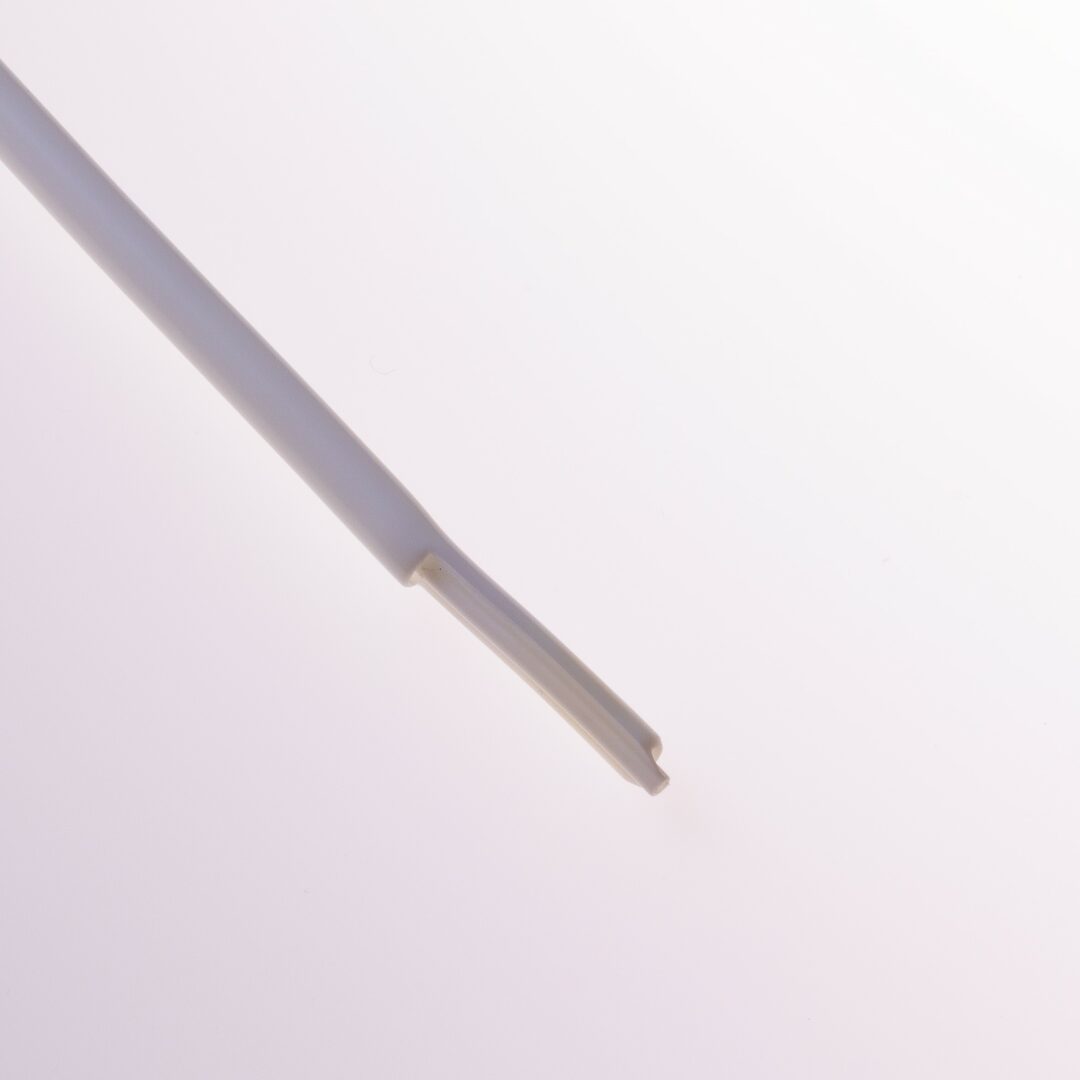

Die beiden Lumina sind im Coaxial – Design angeordnet, bei welchem das arterielle und venöse Lumen ineinander liegen.

Dadurch können die Seitenlöcher 360° am Katheterlumen angeordnetwerden. Dieses Dialysekatheterdesign verhindert das Ansaugen an der Gefässwand.

Die Katheterspitze ist gestuft ( tapered ) mit einem Abstand von3 cm zwischen dem arteriellen und venösen Schenkel.